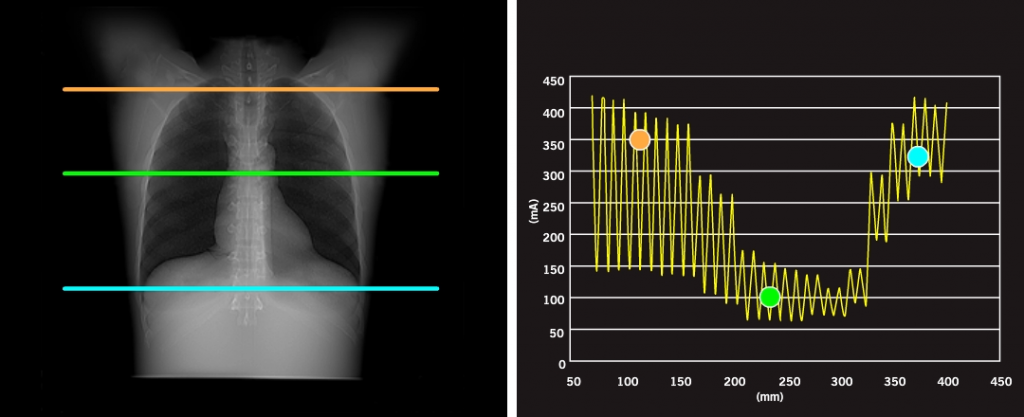

Технологии снижения дозы Canon Medical Systems: Комплексное снижение дозы

AIDR 3D Enhanced с уменьшением дозы 4-го поколения от Canon Medical Systems предлагает превосходное качество изображения. Усовершенствованная система AIDR 3D упрощает снижение дозы за счет адаптивного нацеливания на шум в необработанных данных и пространстве данных изображений. Степень снижения шума оптимизирована для клинических задач и персонализирована для каждого пациента.

Уверенная экспозиция 3D

Модуляция xyz интегрировала оптимизированный рабочий процесс для минимизации дозы. SURE Exposure 3D автоматически оптимизирует ток трубки, чтобы получить максимально качественные клинические изображения при оптимальном воздействии на пациента.